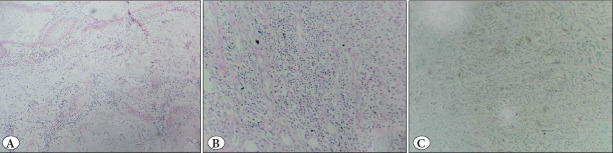

阴沟癌(CC)是分化良好的鳞状细胞癌的一种罕见而独特的临床病理变异。它是一种罕见的生长缓慢的肿瘤,具有类似兔子洞穴(阴沟)的特殊浸润性生长模式。它通常发生在足跖部,也可发生在口腔和生殖器等其他部位。发病机制尚不清楚,不同的作者提出了不同的外伤假说。由于该病通常与良性和其他低级别鳞状细胞癌(SCC)相似,因此必须对其有所了解。CC的诊断具有挑战性,需要反复进行组织学评估和临床相关性分析。在此,我们报告了一例足底和足背的CC病例,患者是一名60岁的男性,曾有多个慢性不愈合溃疡病史,临床上怀疑其为umycetoma,但多次活检仍无结果。

Carcinoma cuniculatum (CC) is a rare and distinct clinicopathological variant of well-differentiated squamous cell carcinoma. It is a rare and slow-growing tumor with a peculiar infiltrative growth pattern resembling rabbit burrows (cuniculi). It usually occurs over the plantar aspect of the foot but can also occur at other sites like the oral cavity and genitals. The pathogenesis is unknown, with various hypotheses of trauma as proposed by different authors. It is essential to be aware of this entity as it commonly mimics benign and other low-grade squamous cell carcinoma (SCC). Diagnosis of CC can be challenging and requires repeated histological evaluation and clinical correlation. Herein, we present a case report of CC of the plantar and dorsal aspect of the foot in a 60-year-old male with a history of multiple chronic non-healing ulcers, which was clinically suspected as eumycetoma and remained inconclusive on numerous biopsies.